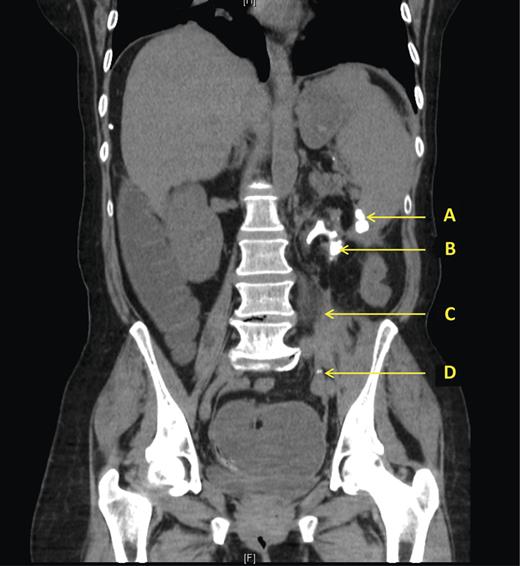

Abdominal X-ray confirmed large bowel obstruction with a cut-off point in the proximal descending colon. A large staghorn calculus was evident in the left kidney with a second smaller well-defined area of calcification just lateral to the renal parenchyma. (Fig. 1)

X-ray showing large left-sided stag horn calculus, with a second adjacent fragment outside the renal parenchyma with evidence of bowel obstruction.